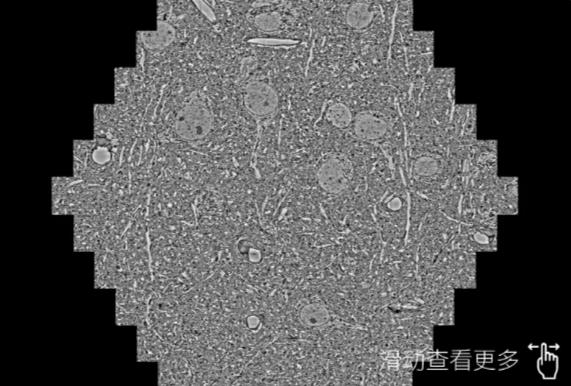

鼠脑切片。左图使用綦江蔡司綦江扫描电镜MultiSEM706对165μmx143pm面积区域成像,耗时仅需1.5秒。右图为鼠脑切片中30μm区域放大效果。样品由芝加哥大学B.Kasthuri提供。

使用蔡司高速綦江扫描电镜MultiSEM对1mm²人脑皮层组织进行高分辨成像,并对其中的各种细胞结构进行三维重构分析。左图展示了2x3mm²组织平面中锥体神经元的三维重构效果。右图显示了局部体积神经元三维重构。图像由哈佛大学chtman实验室提供,渲染图由D. Berger 制作。